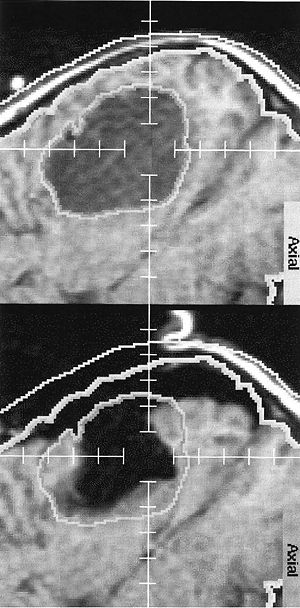

- 4.43 Evaluation of Prostate Segmentation Algorithms for MRI: The PROMISE12 Challenge